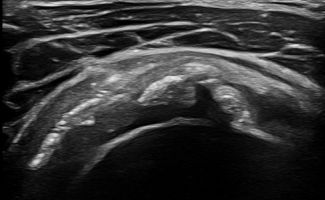

Παθήσεις αρθρώσεων και θυλάκων του ώμου

Με το Υπερηχογράφημα Ώμου μπορεί να εντοπιστεί συλλογή υγρού στα εξής σημεία:

- Υπακρωμιο-υποδελτοειδικός θύλακος

- Yποκορακοειδής θύλακος

- Γληνοβραχιόνιος άρθρωση

Σε περιπτώσεις Ρευματοειδούς Αρθρίτιδας ή Οστεοαρθρίτιδας το υπερηχογράφημα είναι εξαιρετικά σημαντικό για τη διάγνωση υμενίτιδας στην άρθρωση του ώμου.